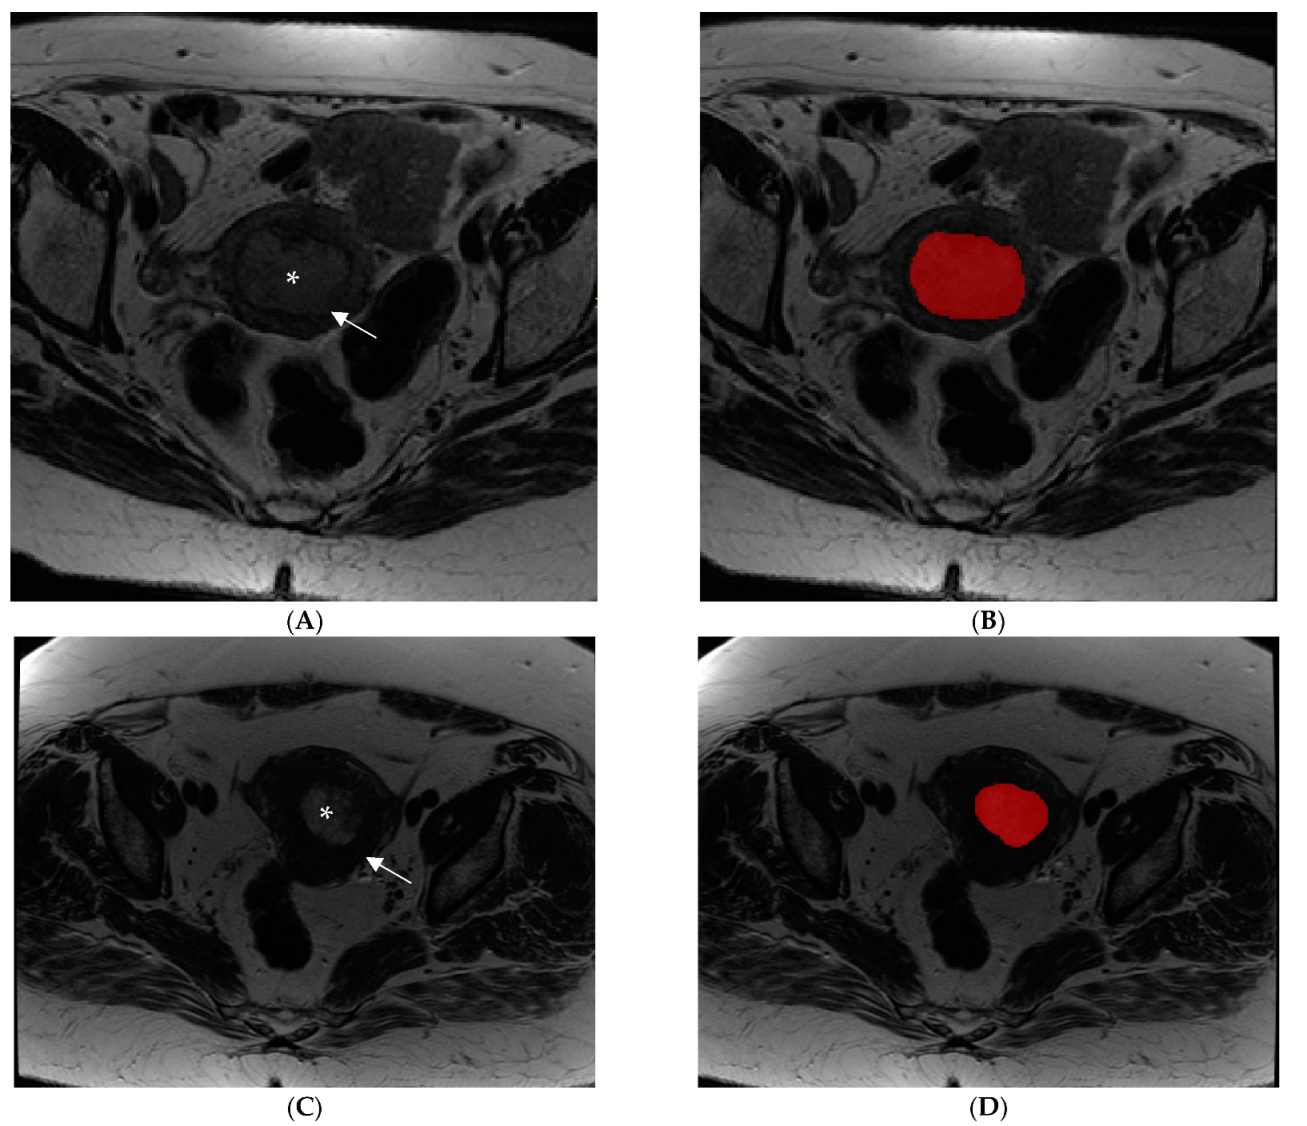

2.3. Image Analysis